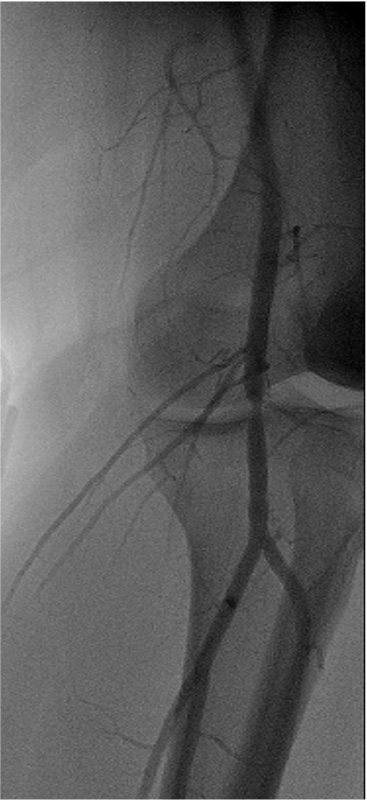

Popliteal entrapment syndrome is a rare condition in which the popliteal artery, which supplies blood to the lower leg and foot, is compressed or squeezed by nearby structures, such as the muscles and tendons at the back of the knee. This can cause reduced blood flow to the lower leg and foot, leading to pain, numbness, weakness, and other symptoms. It is most commonly seen in young athletes and can be treated with surgery or other interventions aimed at relieving the compression of the artery.